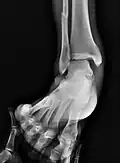

Il y a trois vues radiographiques dans une série complète de cheville : antéropostérieure (AP), latérale et oblique (ou "vue de mortaise"). La vue de la mortaise est une radiographie AP prise avec la cheville tournée vers l'intérieur de 15 à 20 degrés puisque le pied est naturellement tourné vers l'extérieur par rapport à la cheville[8].

Résultats

Sur les radiographies, on peut voir une fracture de la malléole médiale, de la malléole latérale et/ou du bord antéro-postérieur du tibia distal. Le bord postérieur (appelé malléole postérieure) est beaucoup plus fréquemment lésé que la face antérieure du tibia distal. Si les malléoles latérale et médiale sont brisées, on parle de fracture bimalléolaire (certaines d'entre elles sont appelées fractures de Pott (en)). Si la malléole postérieure est également fracturée, on parle de fracture trimalléolaire.[réf. nécessaire]